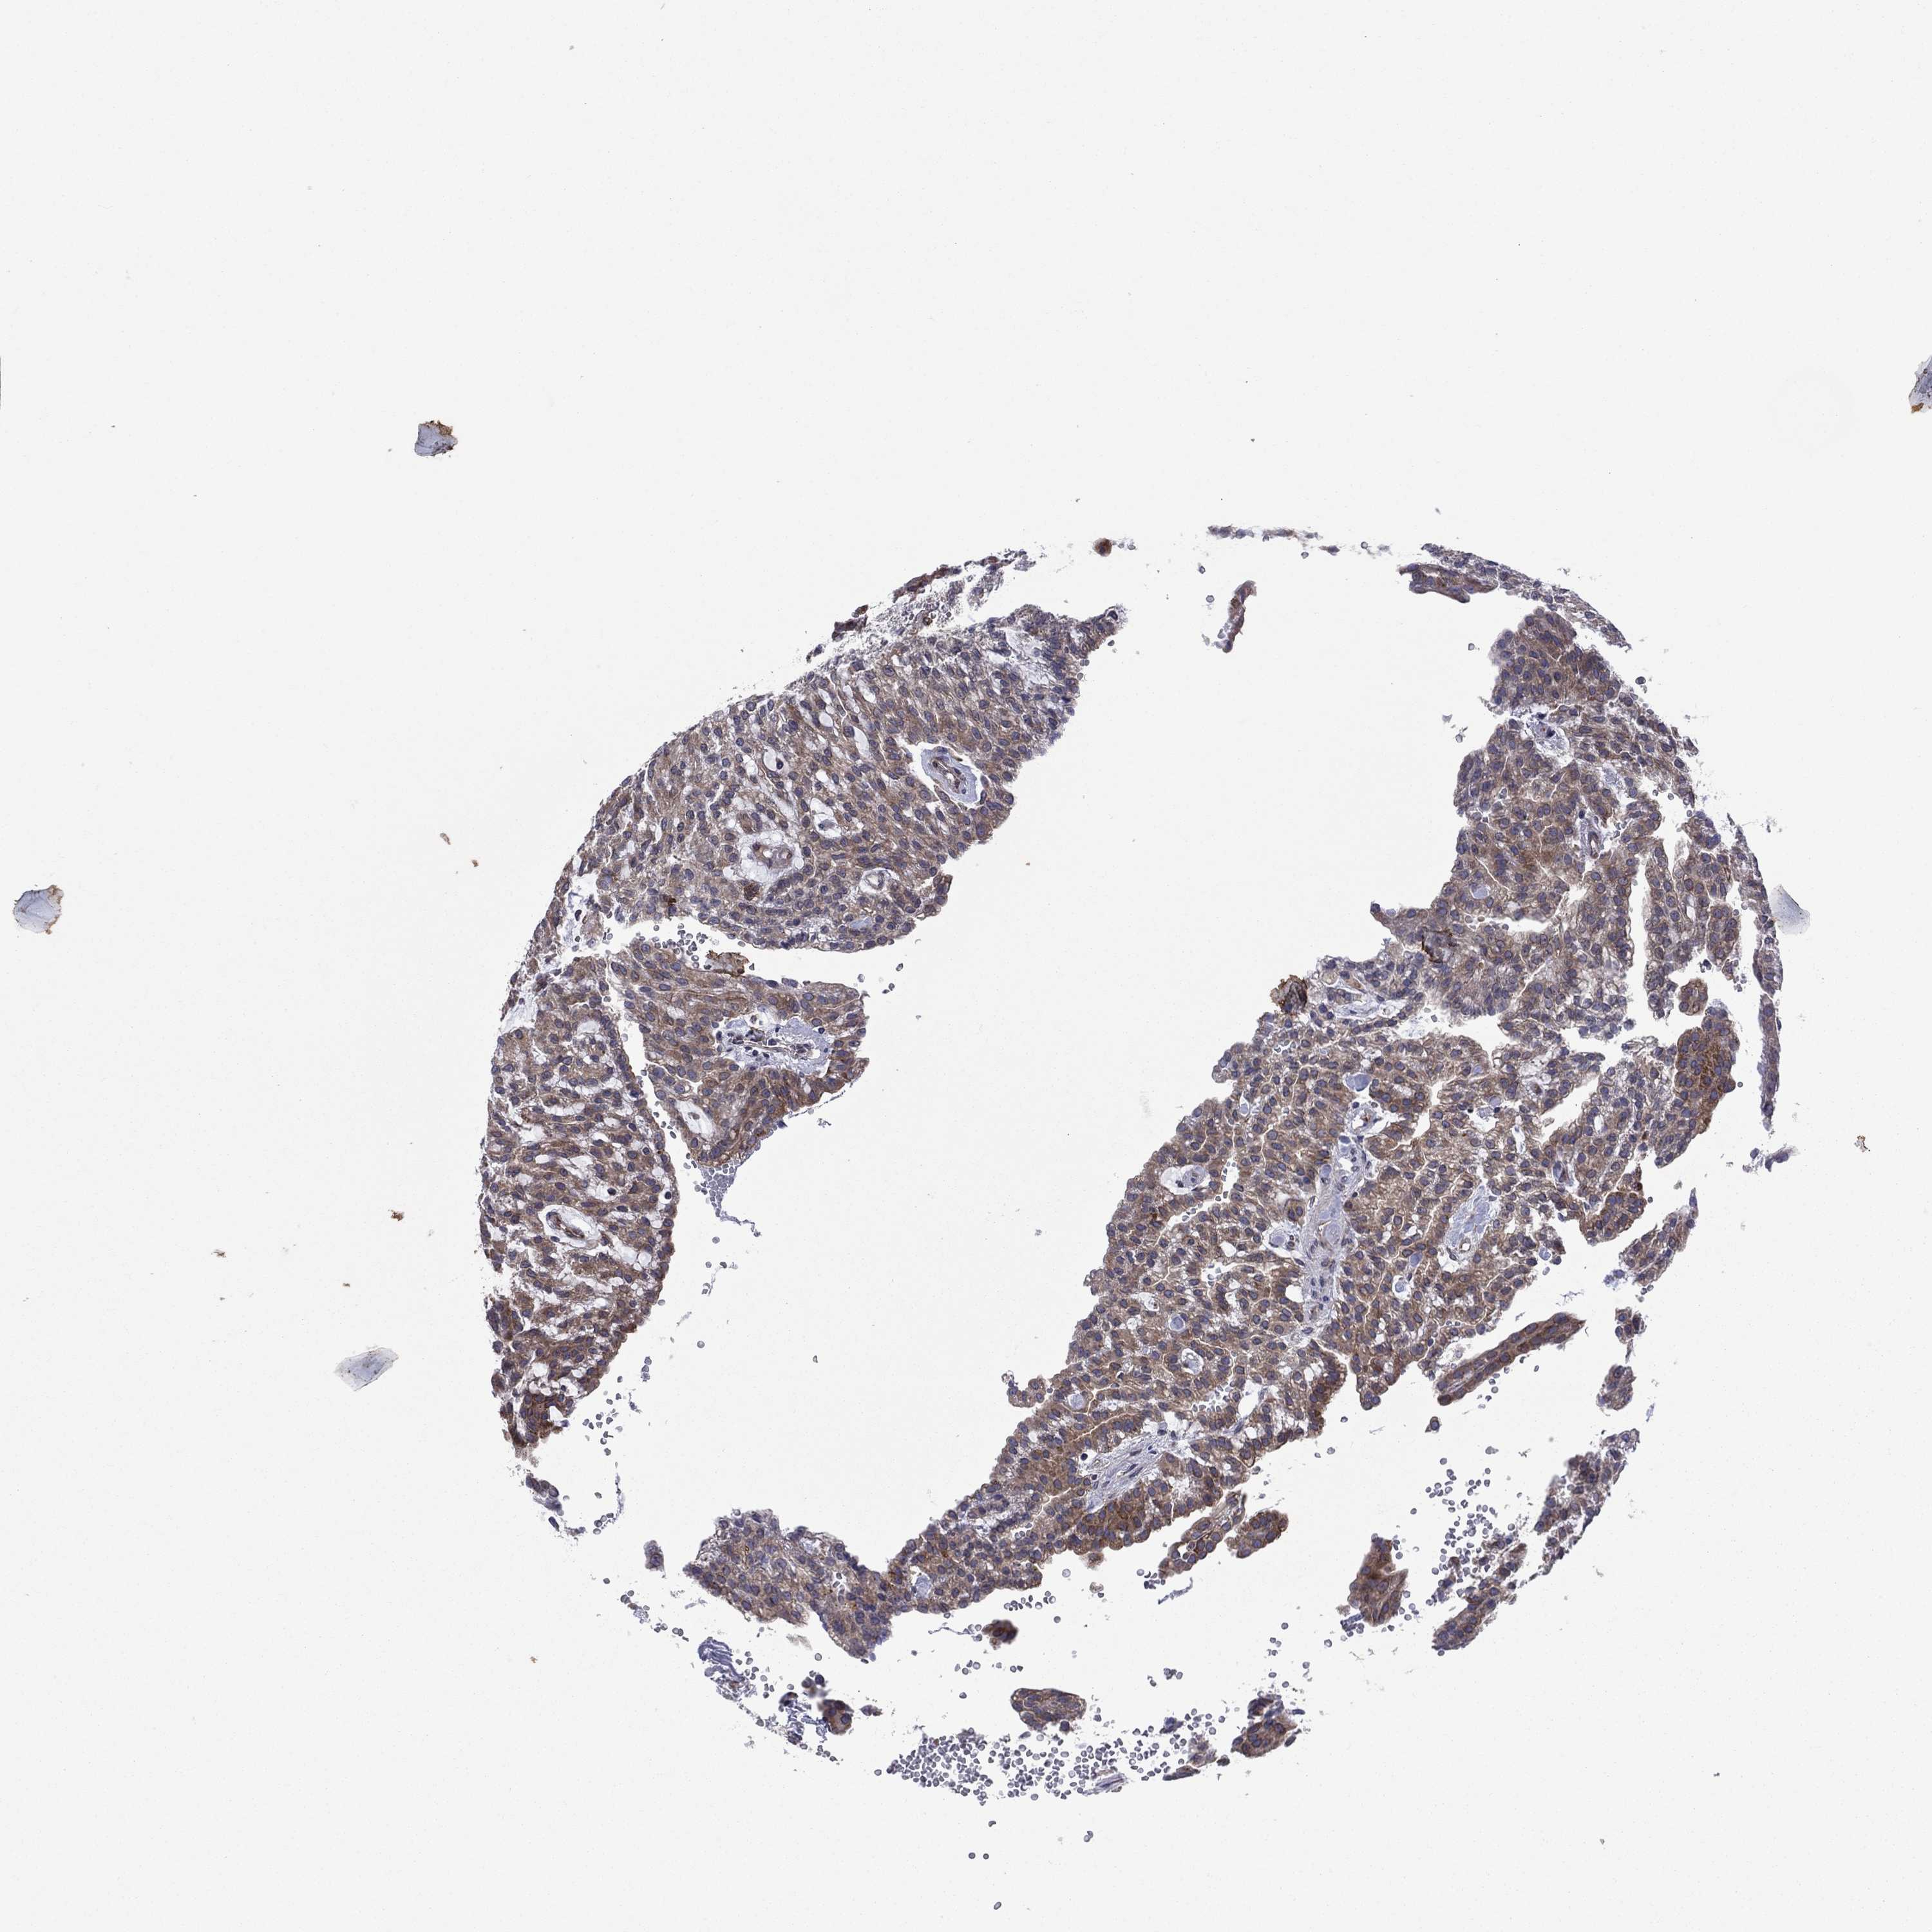

CANCER RENAL CANCER Show tissue menu

KICH TCGA KIRC TCGA KIRC VALIDATION KIRP TCGA PROTEIN RCC CPTAC PROTEIN EXPRESSION